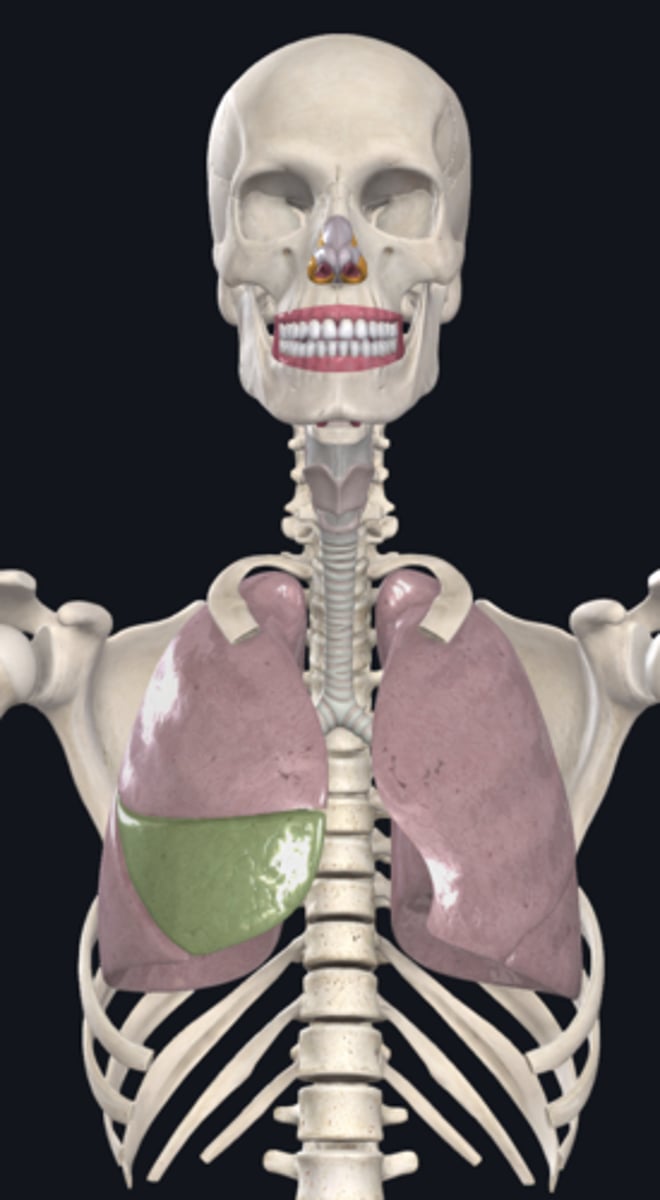

right lung

superior lobe of right lung

middle lobe of right lung

inferior lobe of right lung

left lung

superior lobe of left lung

inferior lobe of left lung

base (diaphragmatic surface)

apex

pulmonary artery

pulmonary vein

hilum of right lung

hilum of left lung

diaphragm